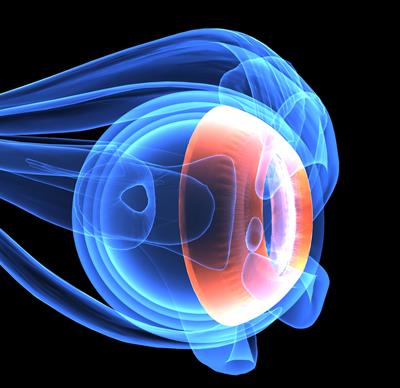

Novel Therapeutic Approaches for the Treatment of Ocular Disease, Volume II

- Kyriaki Thermos

- Stephanie C Joachim

- Giovanni Casini

- Massimo Dal Monte